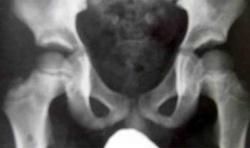

4、X線片顯示股骨頭密度增高,骨骺碎裂,變扁,股骨頸增粗及髖關節部分性脫位等。其X線表現與病理過程有較密切關係。